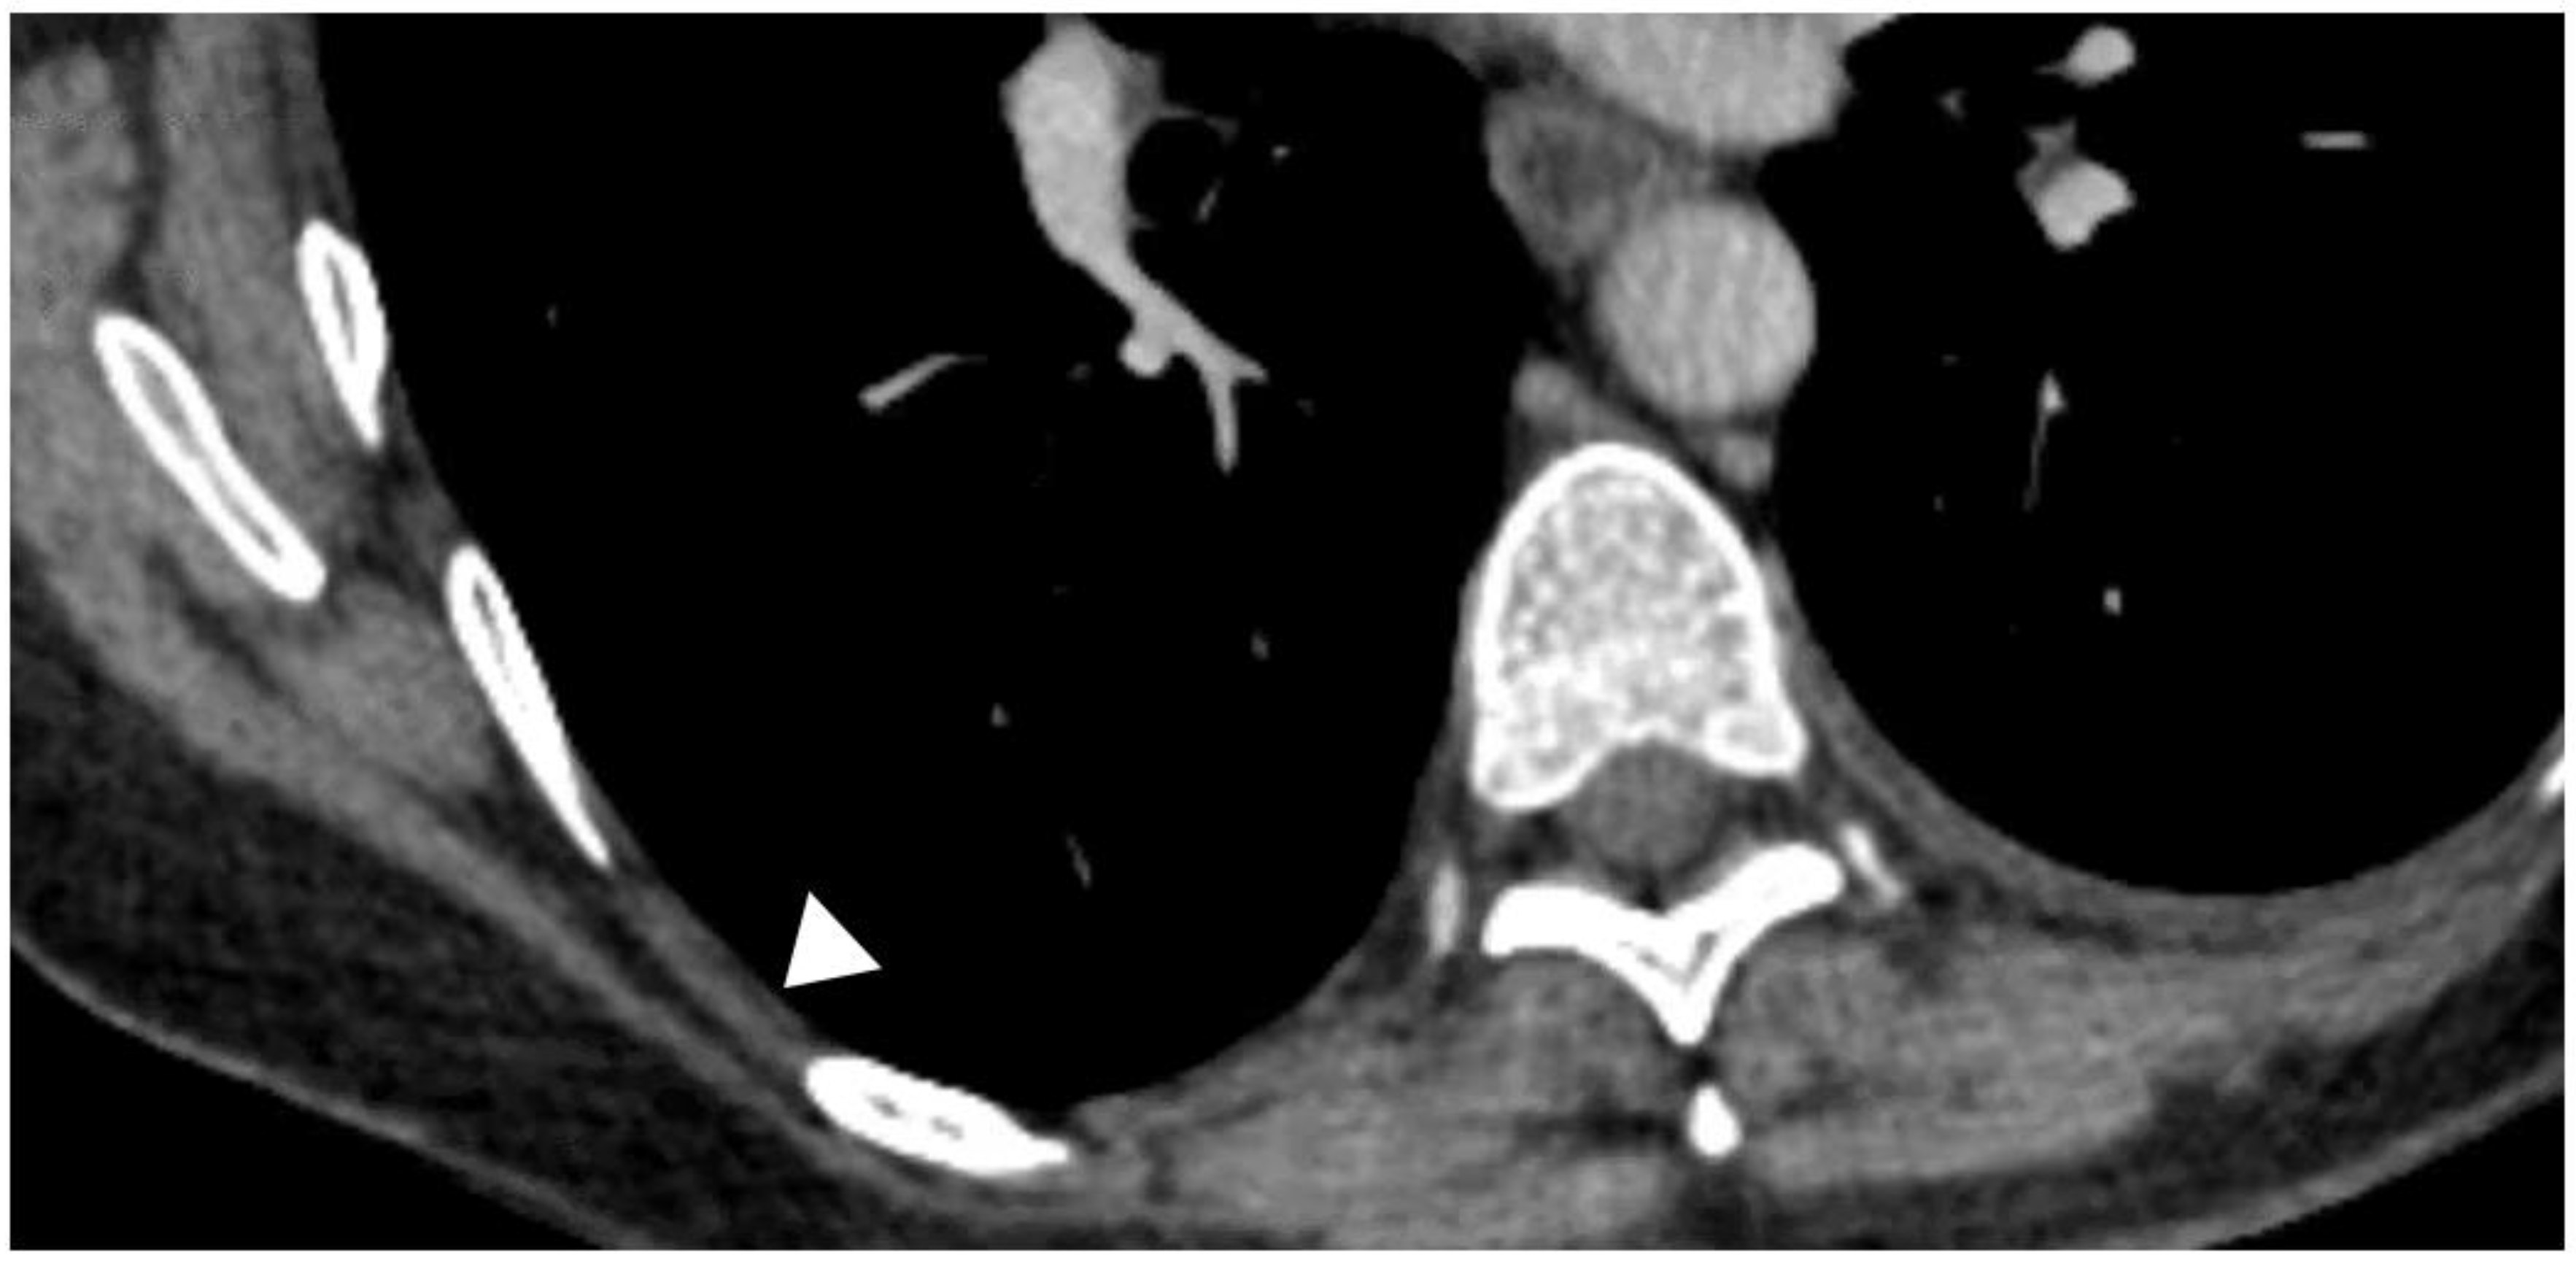

Diagnostic Utility And Clinical Application Of Imaging For Pleural Space Infections Chest

Diagnostic Utility And Clinical Application Of Imaging For Pleural Space Infections Chest

Diagnostic Utility And Clinical Application Of Imaging For Pleural Space Infections Chest

The Frequency Risk Factors And Management Of Complications From Pleural Procedures Chest